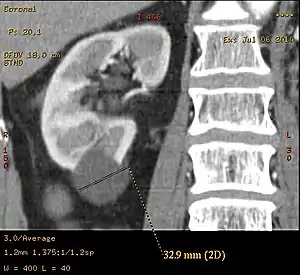

| Renal cyst | |

Diagnosis includes imaging with ultrasound, CT and/or MRI. The least expensive, non-invasive, and most reliable method is ultrasonography but smaller cysts may escape detection, while the resolution of CT and MRI will enable smaller cysts to be captured. However, the increased complexity and expense of CT and MRI is usually reserved for higher risk situations. MRI can be used to monitor the development of cysts and growth of kidneys.